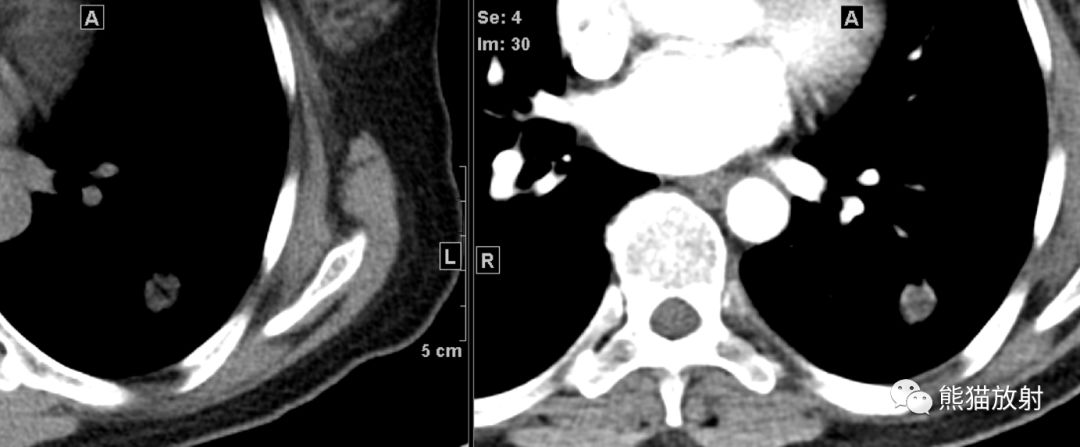

男, 61岁,原发性肺黏液腺癌。左肺下叶被段孤立性周围型肿块,边缘呈“浅分叶”及“毛刺征”,边界尚清,密度欠均匀,平扫CT值约23HU( 白↑) ; 增强动脉期及静脉期CT值分别约35HU、45HU,实质部分呈轻度不均匀强化,静脉期呈“延迟强化”表现。